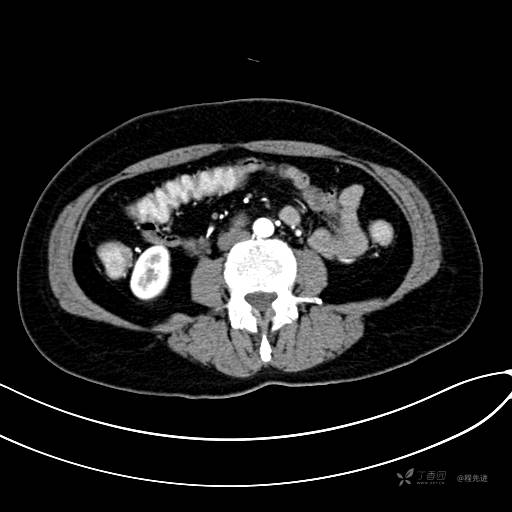

CT增强静脉期